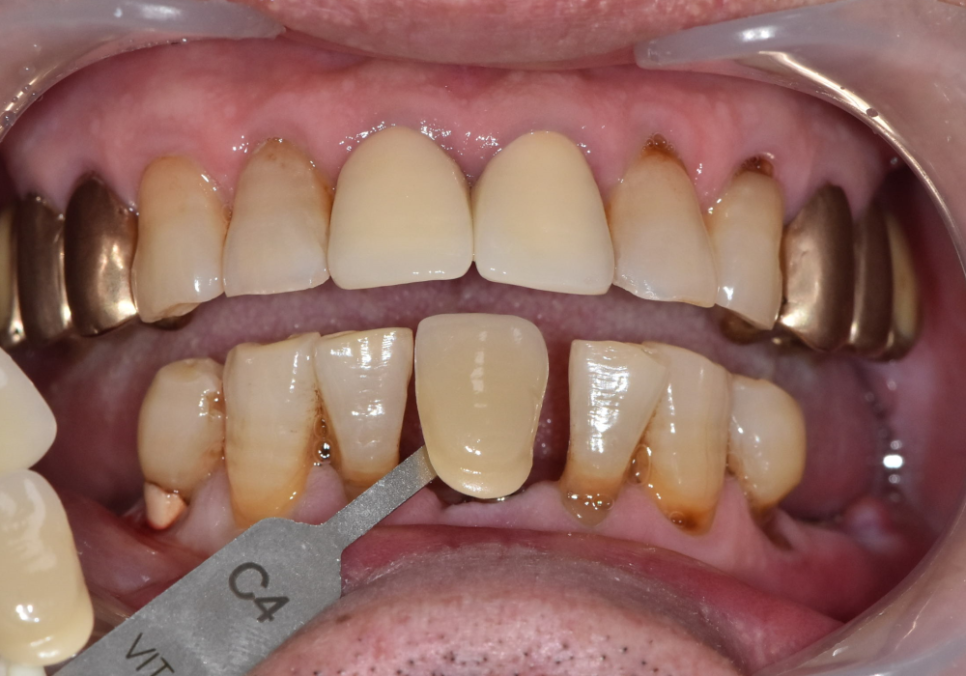

2개월 뒤 완성된 임플란트

2개 발치했는데, 1개만 심어도 된다구요? 강동구 임플란트 가격 줄이는 방법

약 2개월 뒤 보철이 완성됐고,

임플란트를 2개 심지 않더라도

아래 앞니 라인이

자연스럽게 정리되었습니다.

이번 케이스의 핵심은,

환자분의 비용 부담과

구조적, 기능적 안정성을 함께 고려해

무리 없는 설계로

과잉 수술을 줄였다는 점입니다.